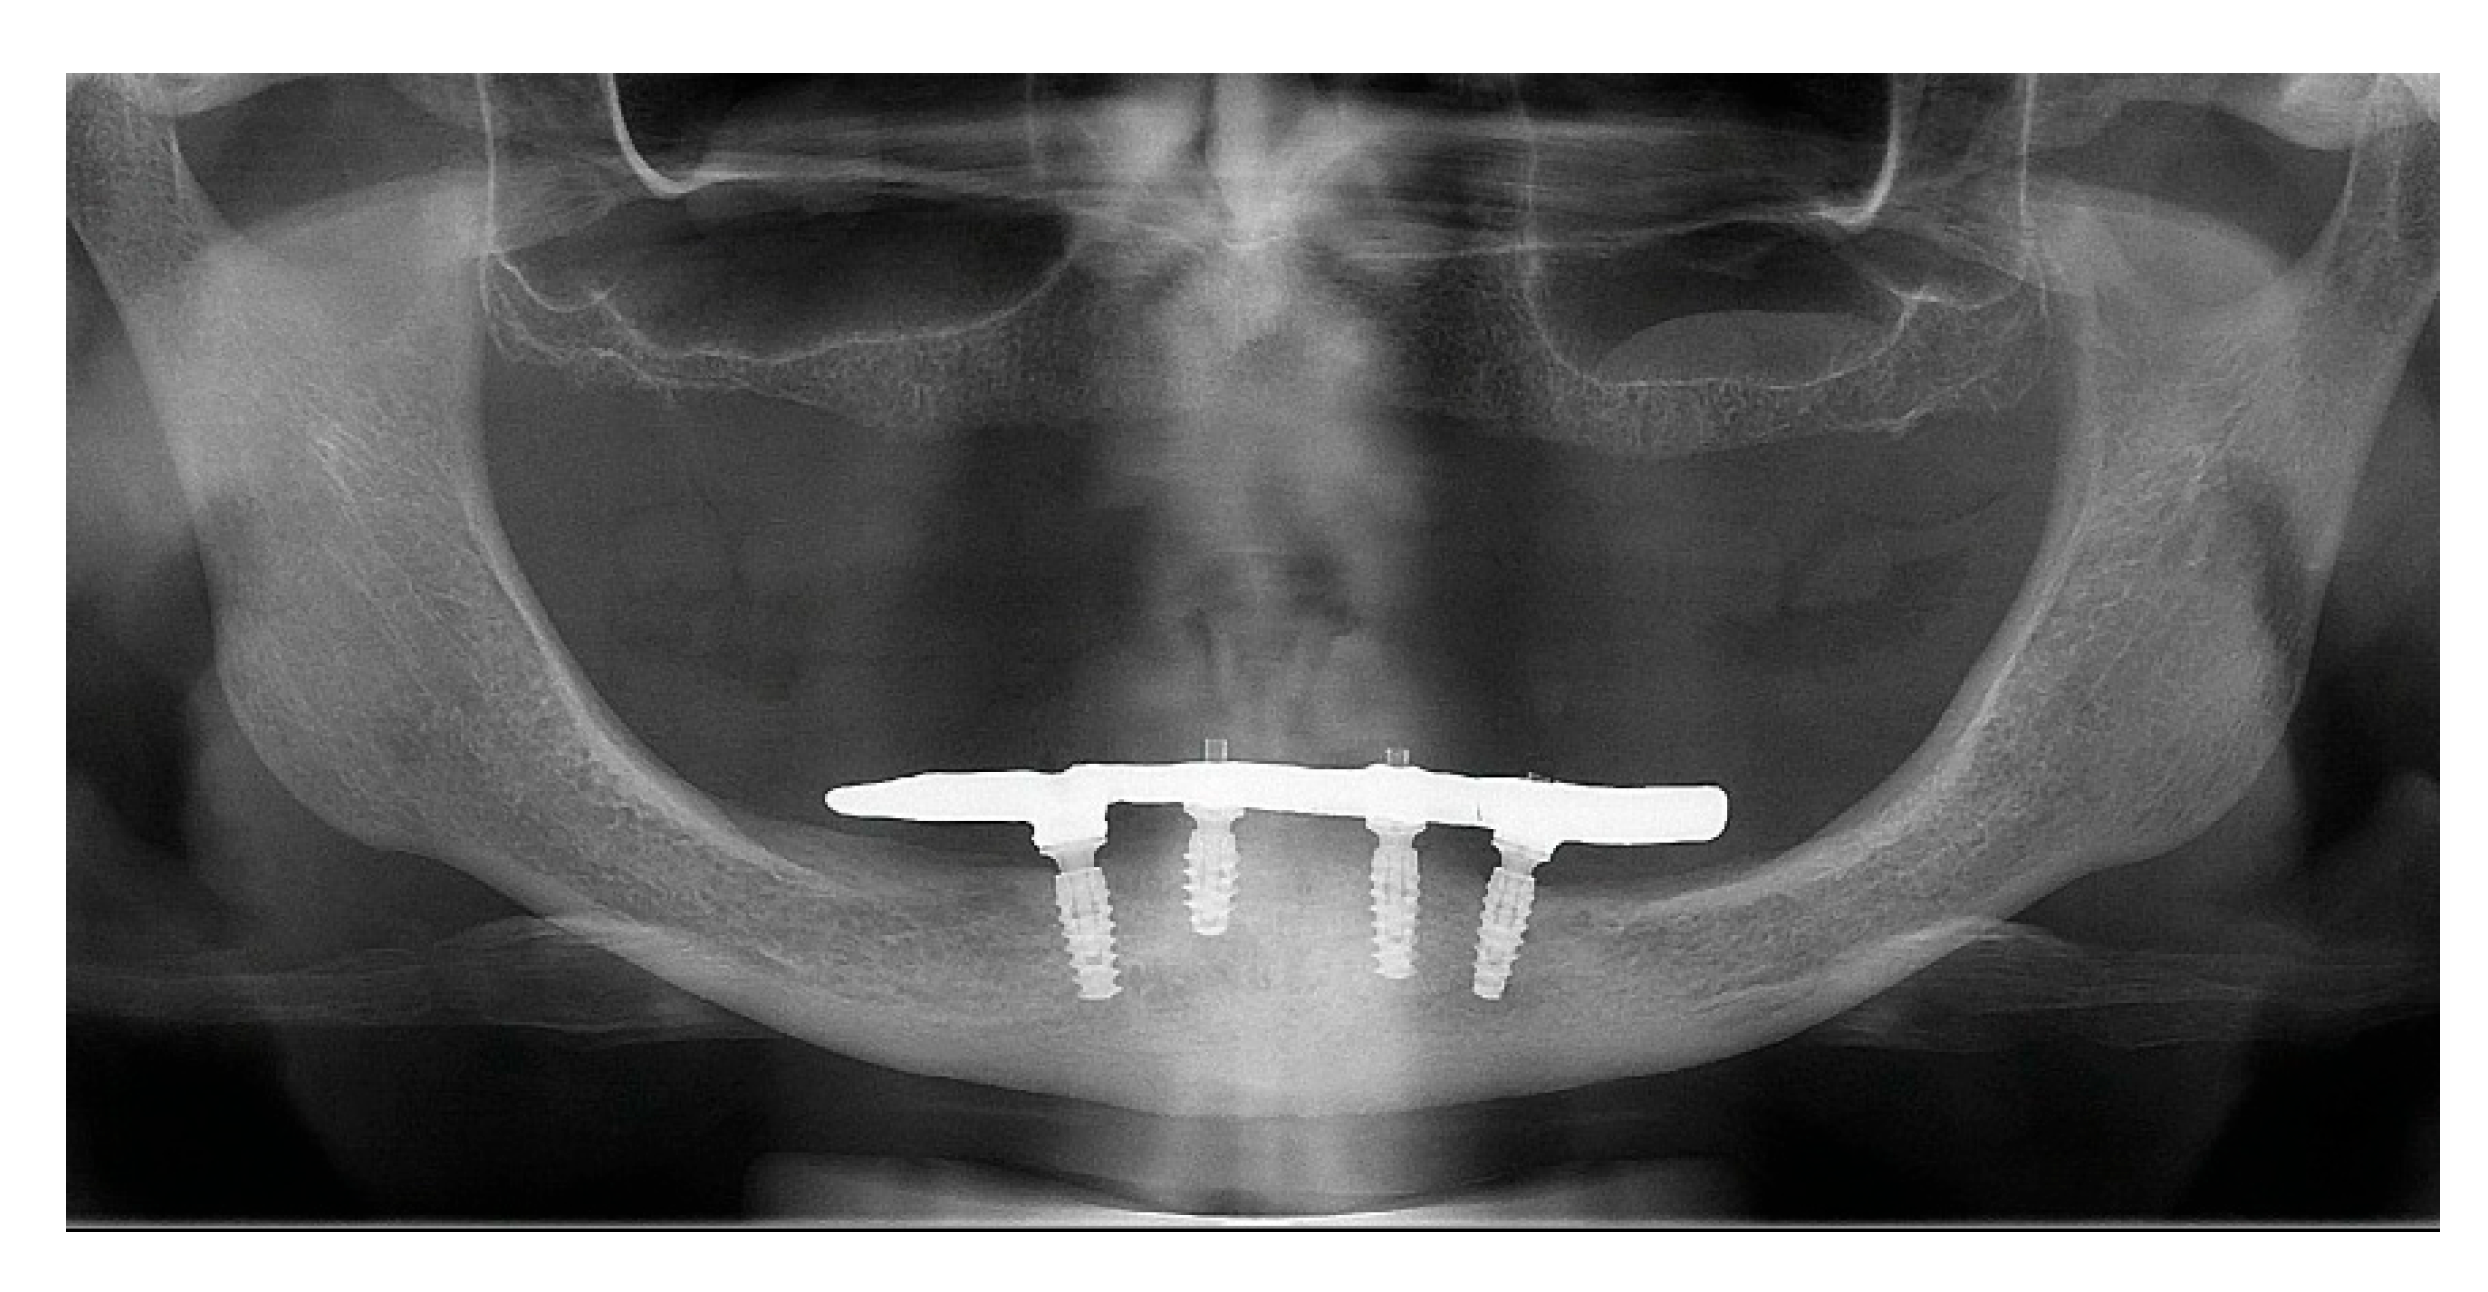

Figure 23. Panoramic radiograph view with 24 months follow-up.

After a healing period of 3 months the patient returned to change que temporary fixed prothesis for a new one, more delicate and with a reinforced metallic bar for a better ferulization of the implants and better dissipation of the stress during function. After removal of the temporary prosthesis we could see the peri-implant mucosa was healthy (Figure 19), without bleeding on probe nor peri-implant sulcus with more than 3mm depth, even around the implants were there were lack of a satisfactory keratinized tissue band, showing us that the patient was being able to maintain the cleansing of the region below the prosthesis. A new fixed rehabilitation over the implants was produced (Figure 20, Figure 21 and Figure 22). 2 years after the surgery we could see on a control panoramic radiograph no signs of bone remodeling above the expected around the implants (Figure 23).